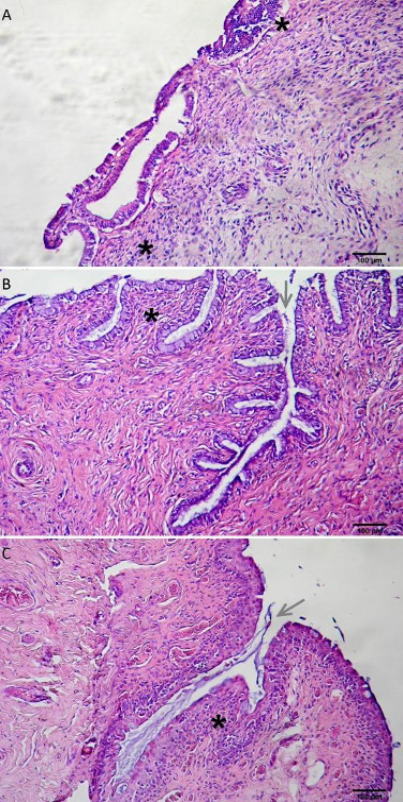

Normal histoarchitecture in samples from control heifers was observed, in agreement with the gestational stage. The presence of embryonic vesicle was detected by ultrasonography on day 29 (Figure 7A). Histological analysis revealed characteristics of a proliferative phase, mainly in the horn ipsilateral to the CL, with gland proliferation, which coincides with the follicular phase of the estrous cycle. This was corroborated by ovarian observation performed at necropsy. At days 40 and 55, conceptus presence was also detected (Figure 7B and 7C).

Figure 7 A. Ultrasonography corresponding to a heifer of the control group at 29 days of gestation. The arrow shows the embryonic vesicle. B. Uterine horn from a heifer of the control group at 40 days of gestation. C. Fetal and conceptus envelopes from a heifer of the control group at 55 days of gestation.